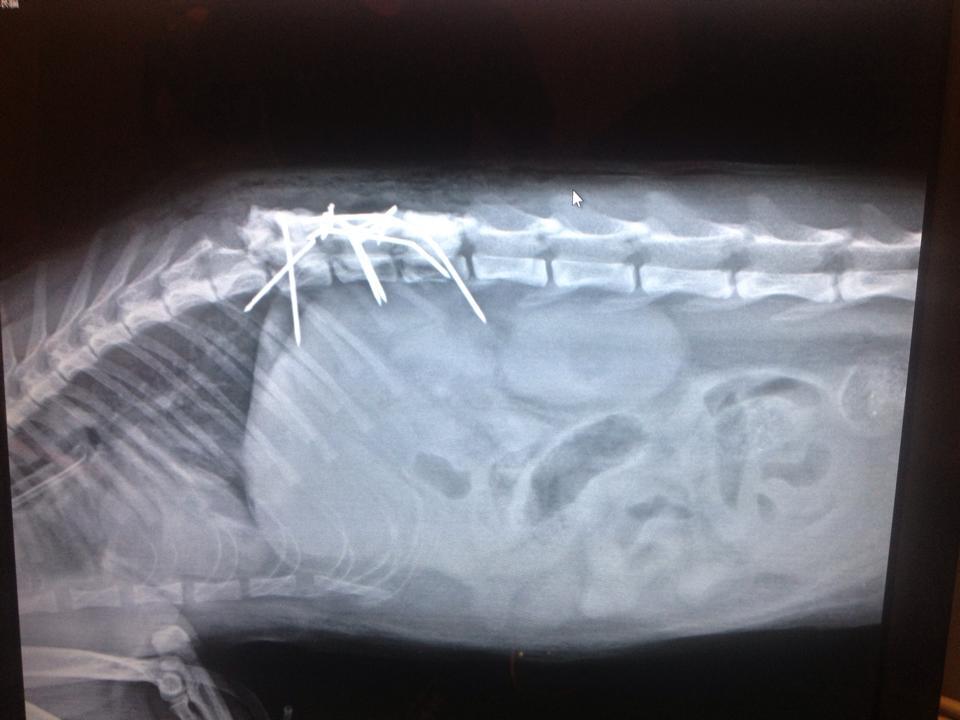

主題: 被車撞,脊椎斷掉的癱瘓貓 申請者姓名: XiangXiang Yan 花色: 申請日期: 2014-11-28 00:59:48 申請者部落格: 申請者臉書網址: 所在縣市/合作醫院: 台中市/羅大宇動物醫院 治療費用: 49000元 需求人數: 53人 已結案 (2015-02-24 12:02:22) 報名人員: Bella Hung(已付款)、Vivian Chen(已付款)、Amberger(已付款)、BigMao(已付款)、Po-Lin Chen x2(已付款)、Chen Ping(已付款)、Chen Ping(已付款)、ERic YU(已付款)、arucat x2(已付款)、陳珍妮(已付款)、Carry Chen x2(已付款)、高小玉(已付款)、Shin-jie Cheng(已付款)、Ning x2(已付款)、Pei-pei Wen(已付款)、FS.NG x2(已付款)、Norman Wu(已付款)、Chenyu Chang(已付款)、Meng-Chen Tseng x2(已付款)、Hsin-Yi Chiao(已付款)、Ariel Huang(已付款)、Luis x8(已付款)、櫻花妹(已付款)、Shannon x2(已付款)、徐雅嬪(已付款)、大皮(已付款)、Bubu Wang(已付款)、菲小比(已付款)、Mia Tsai、老王(已付款)、Winnie(已付款)、Luis x8(已付款)、陳伊潔(已付款)、 候補人員: 動物病情說明: 11/11大約晚上10:00,在馬路中間發現一隻被車撞,倒在地上抽蓄的貓咪,立刻送往附近的全國動物醫院,掃超音波,照X光,發現脊椎斷掉,嘴巴和腳擦傷流血。

醫生說手術的黃金時間是一天內,所以安排11/12手術。

手術前,貓咪的後腳都有一點點知覺,但癱瘓無法行走。